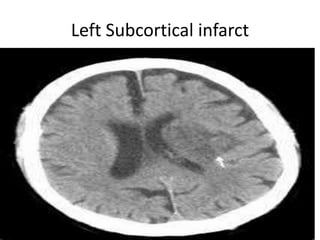

Left Subcortical infarct

Vascular Insults • SubarachniodHemorrhage. • Lobar and basal ganglia bleeds. • Ischemic strokes. • Venous infarcts. • Disections